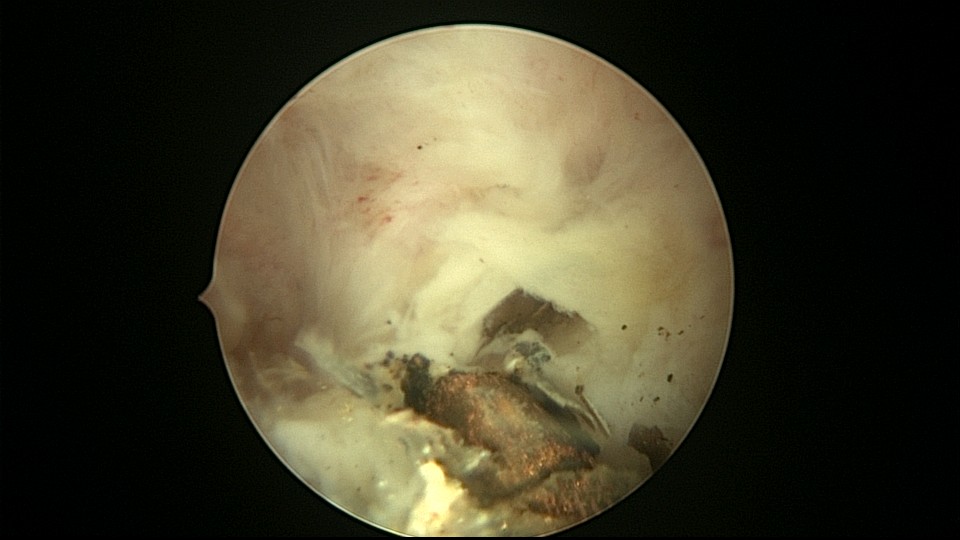

患者48岁,G3P1,顺产1次。安环10年,绝经1年,外院取环失败,子宫穿孔,腹部平片无异常。宫腔镜见宫腔广泛致密粘连,V型环与粘连组织嵌顿,取环钩盲视下多次尝试钩取节育环,均失败。取环钩循镜鞘外侧进入宫腔,直视下钩住节育环,顺利取出。再次置镜寻找子宫穿孔处并进入盆腔,见网膜脂肪组织,确认无活动性出血及盆腔积血,结束手术。